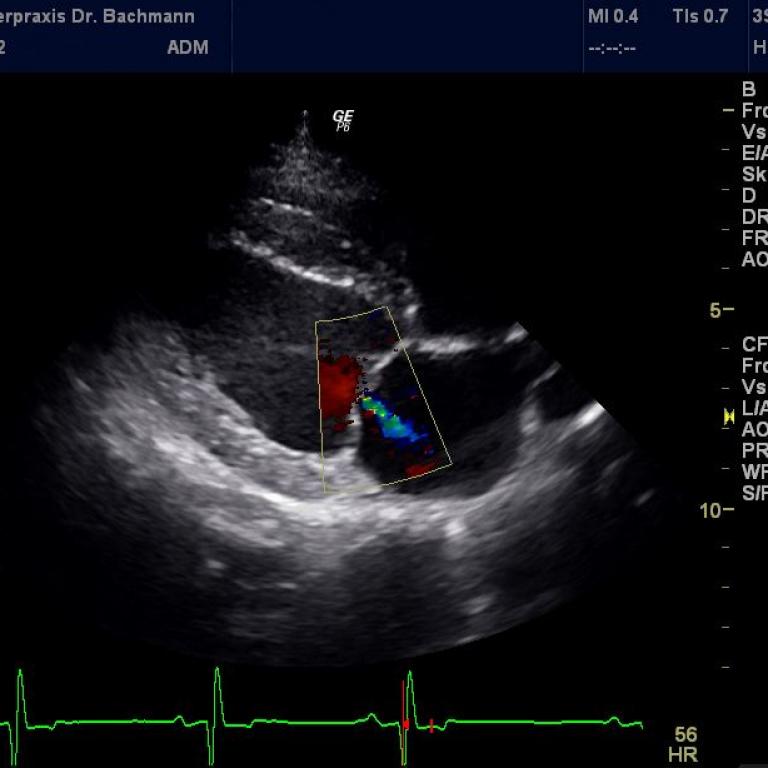

Eine leistungsstarke Röntgenanlage, ein modernes High-End-Ultraschallsystem und ein Videoendoskop ermöglichen uns ein breites Spektrum an bildgebender Diagnostik.